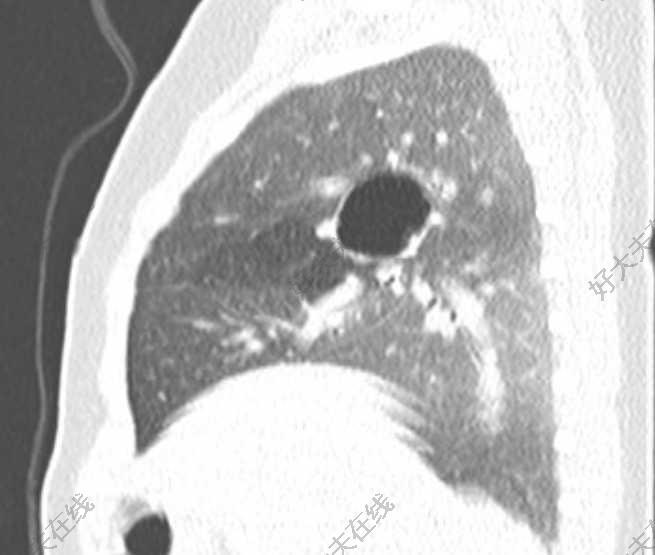

临床特征CPAM的表现多样。常规产前超声检查可发现许多病例。早期的回顾性研究提示,产前诊断的CPAM婴儿中,多达2/3在出生时有症状。更新的数据显示,仅约25%的新生儿患者有症状。这种差异可能反映了产前超声诊断技术的改善,导致现在能够检出更小的病变,而这类病变往往无症状。产前表现 — CPAM的产前超声表现轻则为偶然发现的囊肿样病变,重则为巨大肺部受累。根据胎儿超声检查,约50%的病例在后续妊娠期间病变似乎消失,但其中大多数在胎儿出生后仍可通过影像学检查发现。据报道,出生时仍存在病灶的患者中,小部分可在出生后自行完全消退。一项回顾性研究提示,CPAM的大小在胎龄约25周时达到峰值,病变缩小则结局较好,除非存在严重水肿。CPAM的产前诊断、病程和处理详见其他专题。产前影像学 — CPAM是较常见的肺部病变产前诊断,但出生患病率非常低。产前诊断通常经超声检查得出。依据超声结果和大体解剖学可对产前出现的CPAM进行分类。微小囊性病灶由直径<5mm的囊肿构成,表现为强回声和实性,而巨大囊性病灶含有1个或以上直径>5mm的囊肿。CPAM容积比(CPAMvolumeratio,CVR)是CPAM容积与胎儿头围的比值,可作为预后指标。产前MRI评估有助于区分CPAM与其他肺部异常,包括支气管肺隔离症(bronchopulmonarysequestration,BPS)、先天性膈疝以及先天性大叶性肺气肿。产前检出CPAM的婴儿中约25%也存在其他结构性异常,这些病例大多为2型CPAM。应对伴有这类异常的胎儿行核型分析,而仅有CPAM的患者则通常无染色体异常。水肿的发生 — CPAM可引起腔静脉阻塞及心脏移位和压迫,造成血流动力学改变,导致5%-40%的胎儿出现水肿。具有以下特征的胎儿水肿风险最大:病变较大、妊娠晚期时病变仍持续存在,以及微小囊性病变。作为CPAM容积相对于胎儿头围的指标,CVR尤其能预测水肿风险的增加。新生儿期无症状患者 — 产前诊断为CPAM的患者中,约有3/4在出生时无症状。出生时无症状CPAM的自然病程尚不十分明确。目前清楚的是,一部分这些婴儿会在几岁以内出现并发症(主要是感染),但不同病例系列研究中显示的并发症发生率差异很大。除4型CPAM外,其余CPAM为恶性的风险极低,但1型病变也有一定恶性潜能。由于不能确定感染和恶性肿瘤的风险,针对这些患者的治疗方式存在争议,在下文中有讨论。有症状患者 — 其余25%产前诊断为CPAM的患者在出生时有症状。例如,一项纳入89例产前诊断为CPAM婴儿的病例系列研究中,22例患者有呼吸异常,其中12例有重度呼吸窘迫。病灶越大(如,CVR>0.84),发生呼吸窘迫的可能性及其严重程度也越高。其他可预测在出生时会发生呼吸窘迫的超声表现包括纵隔移位、羊水过多和腹水。不同CPAM类型有一些不同的临床特征:0型CPAM伴有气体交换严重受损,婴儿在出生死亡。新生儿出现的CPAM大多为1型。对于有症状的患者,典型体征包括呼吸过速、呼吸费力伴呼噜音和三凹征,以及发绀。根据空气潴留的程度,大的囊肿可能扩张,引起呼吸窘迫。2型CPAM患者由于大多(高达60%)伴有其他先天性畸形,通常会在出生后不久诊断。其呼吸系统的起病体征和症状与1型CPAM相似。3型CPAM最为严重(除0型之外,0型患者在出生时均死亡)。3型病灶较大,可累及整个肺,通常有胎儿水肿和肺发育不良。婴儿可能在出生时死亡,或者在出生后很快出现重度进行性呼吸窘迫、发绀和呼吸衰竭。在过去,3型CPAM以男性胎儿患者为主。4型CPAM可出现在新生儿期,可能难以同1型相鉴别。有报道显示,一些患者出现了自发性气胸。由于许多4型病变可能由PPB引起,如果婴儿存在CPAM和气胸,均应高度怀疑为恶性。儿童期表现 — 约1/3的CPAM在新生儿期之后被诊断。通常为1型、2型或4型,且病变通常小于在出生时有呼吸系统症状的CPAM。较年长儿童的常见表现为复发性肺炎。其他主诉包括咳嗽、呼吸困难和/或发绀。体格检查发现包括:病灶区呼吸音减低、过清音,以及胸壁不对称伴患侧凸出。CPAM还可表现为自发性气胸。由于气胸最常见于4型CPAM,而4型CPAM与恶性肿瘤相关,只要CPAM儿童出现气胸,都应高度怀疑病变为恶性。一项研究报道了12例在6月龄至23岁(平均6.7岁)被诊断为CPAM的患者,其中9例表现为复发性肺部感染,1例表现为气胸,另外2例为偶然发现。11例行手术切除了CPAM,其中7例为1型,4例为2型。

先天性肺气道畸形诊疗中国专家共识(2021版)解读

先天性肺囊性疾病科普(一):先天性囊性腺瘤样畸形CCAM(肺囊肿)